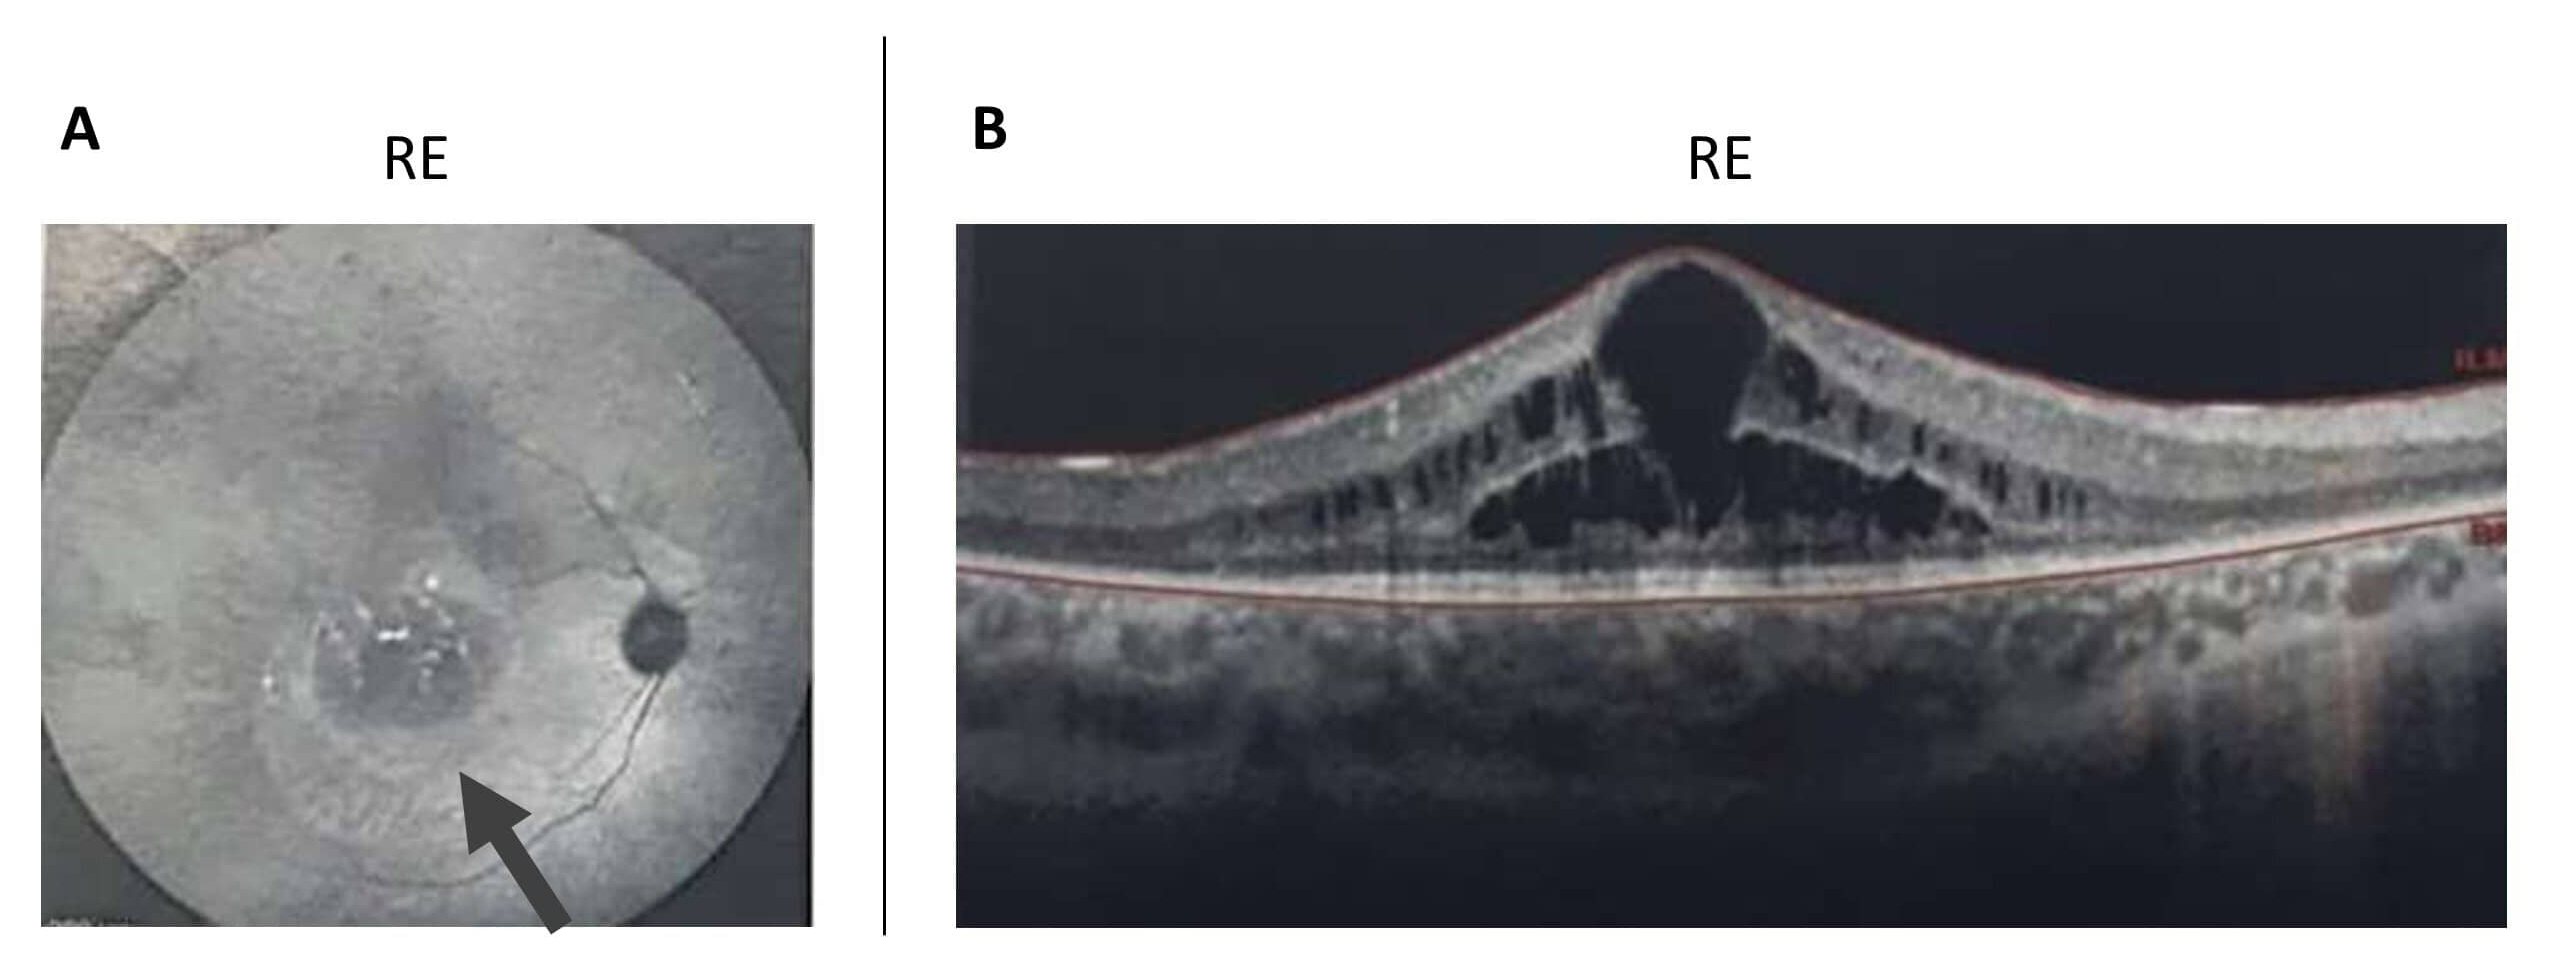

Figure 3. Retinal autofluorescence and OCT imaging in patient RP2:03. A: Retinal autofluorescence examination of the right eye (RE) of patient RP2:03, presenting a large hypoautofluorescent central

macular area, marked by an arrow, and some hyper-autofluorescence in the inferior area of the optic nerve head. B: Macular optical coherence tomography (OCT) of the RE discloses cystoid macular edema and the loss of the ellipsoid zone

outside the fovea, reflecting rod photoreceptor loss.